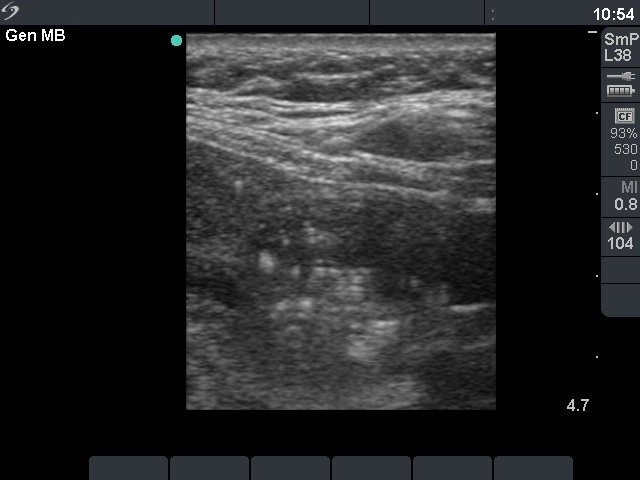

Second examination 14 months later (second row of images)

The whole thyroid increased in volume by 38%. Surgery was advised

Histopathology: benign hyperplastic nodular goiter.